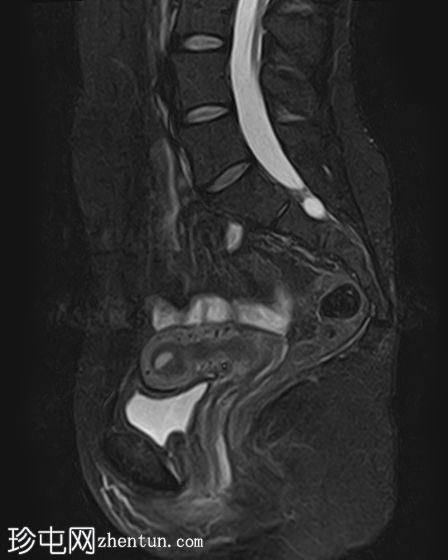

5.jpg

矢状位

T2

卵巢相关囊性病变边界相对清晰。信号特征可能因出血时间而异。

T2 加权成像通常显示高信号。 T2 阴影征提示存在慢性血液产物,更像子宫内膜异位症。

本例卵巢囊肿呈中等 T1 信号,类似于肌肉信号,T2 信号高,伴有薄内隔和外周壁强化。但无内部强化或弥散受限。STIR 序列显示与 T2 一致的信号,无任何脂肪成分。该表现提示卵巢出血性囊肿处于早期或消退期。

建议在下一个月经周期(通常在 6 至 8 周内)进行盆腔超声随访,以确保囊肿消退,因为大多数出血性囊肿往往会自行消退。如果病变持续存在或扩大,可能需要进一步评估。